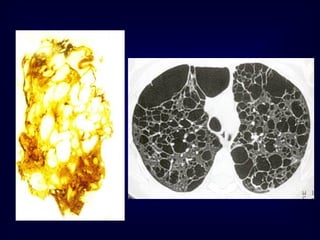

A classic reticular pattern is seen with pulmonary fibrosis, in

spaces along the pleural margins and lung bases

This 50-year-old man presented with end-stage lung fibrosis

PA chest radiograph shows medium to coarse reticular

B: CT scan shows multiple small cysts (honeycombing) involving

predominantly the subpleural peripheral regions of lung. Traction

bronchiectasis, another sign of end-stage lung fibrosis.